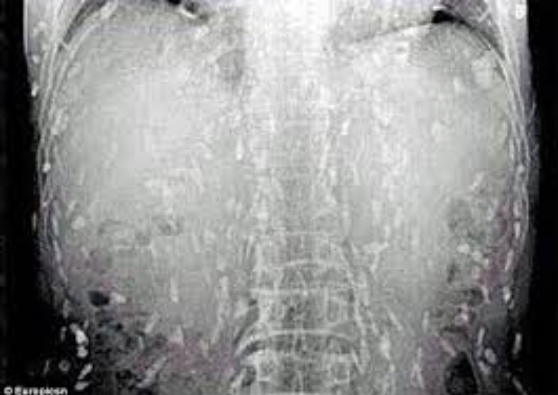

Mans entire body flooded with worms after eating sushi 3.png

Mans entire body flooded with worms after eating sushi 3.png (321.54 KiB) Viewed 24378 times

Rest assured there is treatment: The standard treatment for diphyllobothriasis, as well as many other tapeworm infections is a single dose of Praziquantel, 5–10 mg/kg PO once for both adults and children. An alternative treatment is Niclosamide, 2 g PO once for adults or 50 mg/kg PO once.One should note that Praziquantel is not FDA approved for this sign and Niclosamide is not available for human use in the United States. Another interesting potential diagnostic tool and treatment is the contrast medium, Gastrografin, introduced into the duodenum, which allows both visualization of the parasite, and has also been shown to cause detachment and passing of the worm.